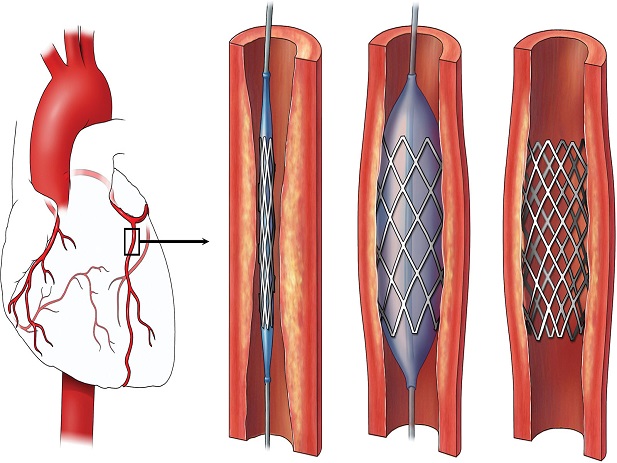

قیمت: 48٬000 تومان - دسته بندی فایل: پاورپوینتپاورپوینت Stent(استنت)

فروش ویژه فایل های پاورپوینت حرفه ای Stent(استنت) با تخفیف استثنایی فقط 72000 هزار تومان تعداد اسلاید : 37 اسلاید